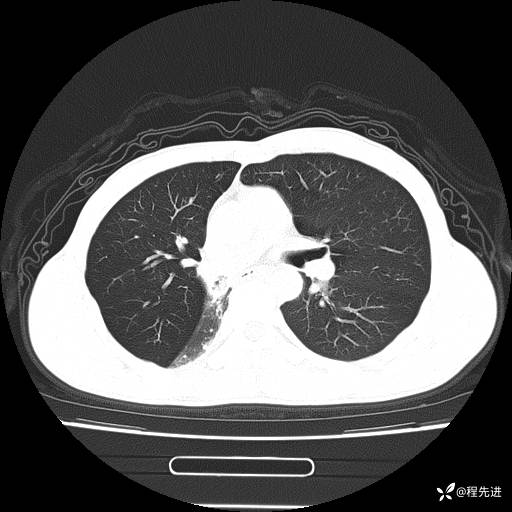

患者性别:男

患者年龄:49岁

主诉:咳嗽、胸痛1周

简要病史:1周前受凉感冒后开始出现咳嗽症状,阵发性连声咳,痰多,黄白痰,不易咳出,伴胸痛、气紧、胸闷,右侧为主,活动用力、呼吸时胸痛明显,曾在当地诊所贴敷膏药仍疼痛

体格检查:T:36.3 ℃ P:80 次/分 R:20 次/分 BP:120/88 mmHg,指脉氧饱和度97%,意识清晰,呼吸平稳,右侧第二、三肋骨压痛,可见膏药贴敷,皮肤无异常,双肺呼吸音粗,未闻及干湿性啰音。心率80次/分,节律整齐,无杂音。腹平软,全腹无压痛无反跳痛

临床诊断:社区获得性肺炎

CT平扫: